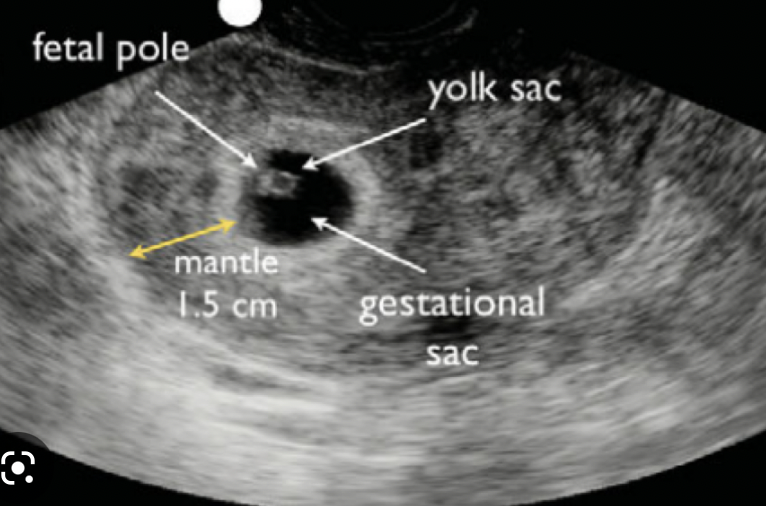

What 3 features are looked for on transvaginal US to determine the viability of a pregnancy?

A

• mean gestational sac diameter

• foetal pole + crown-rump length

• fetal heartbeat

mean gestational sac diameter

these appear sequentially so as each feature develops, the previous becomes less relevant in determining viability of a pregnancy

How is an anembryonic pregnancy diagnosed on transvaginal USS?

• a fetal pole is expected once mean gestational sac diameter is 25mm or more

• if the MGSD is >25mm and there is no fetal pole, scan is repeated after 1 week

• if the fetal pole is still not present, this is an anembryonic pregnancy